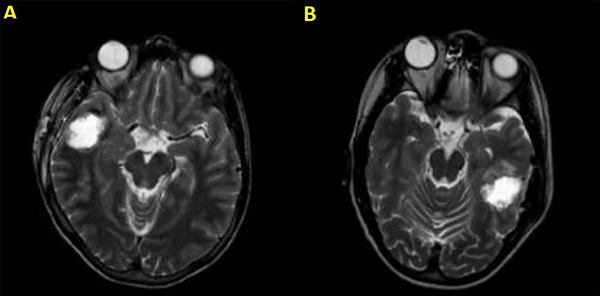

La RM puede identificar lesiones del lóbulo temporal y otras anomalías con una sensibilidad y especificidad de alrededor del 90%. Una amplificación anormal relativa de la señal en la materia gris/blanca del lóbulo temporal, atrofia del fórnix ipsilateral, dilatación del cuerno temporal del ventrículo lateral y desdibujamiento de los límites entre la materia gris y blanca del neocórtex temporal son todos criterios diagnósticos significativos de RM a tener en cuenta. La esclerosis hipocampal del lado derecho se muestra en las Figuras 1A y 1B, y una malformación cavernosa del lóbulo temporal se ve en las Figuras 1C y 1D. Se utilizaron los siguientes procedimientos no invasivos en esta muestra para evaluar a los pacientes antes de la cirugía: RM de 1.5 y 3T, monitoreo de EEG nocturno con video, examen físico neurológico y evaluación semiología. Una vez localizada el área epiléptica, la extensión de la resección quirúrgica fue determinada por electrocorticografía intraoperatoria (ECoG). Además, preoperatoriamente, los pacientes pediátricos se sometieron a evaluaciones neuropsicológicas que incluyeron pruebas estandarizadas adecuadas para la edad para evaluar la cognición, el lenguaje, la memoria, la atención, la resolución de problemas, el análisis visual, espacial, perceptual, habilidades académicas, funciones motoras y sensoriales, comportamiento, personalidad, estado emocional y funcionamiento adaptativo. Se presume el área de disfunción preexistente basada en los datos recopilados, se establece la lateralización de la zona del habla y se evalúan los riesgos y beneficios de la cirugía.4

Figura 1. Esclerosis hipocampal derecha mostrada en las Figuras A y B; y malformación cavernosa del lóbulo temporal en las Figuras 1C y 1D.